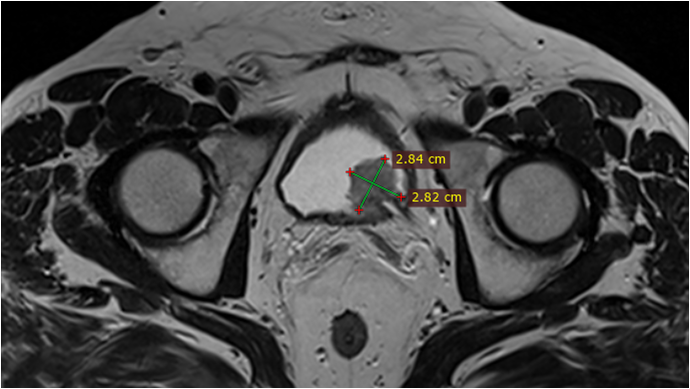

01.2018 була операція – протезування черевного відділу аорти.

Резекція черевного відділу аорти, протезування черевного відділу аорти (01.2018). ГПМК (2014).

Під час засідання мультидисциплінарного консиліуму колектив фахівці постановив:

Провести резекцію правої нирки у плановому порядку